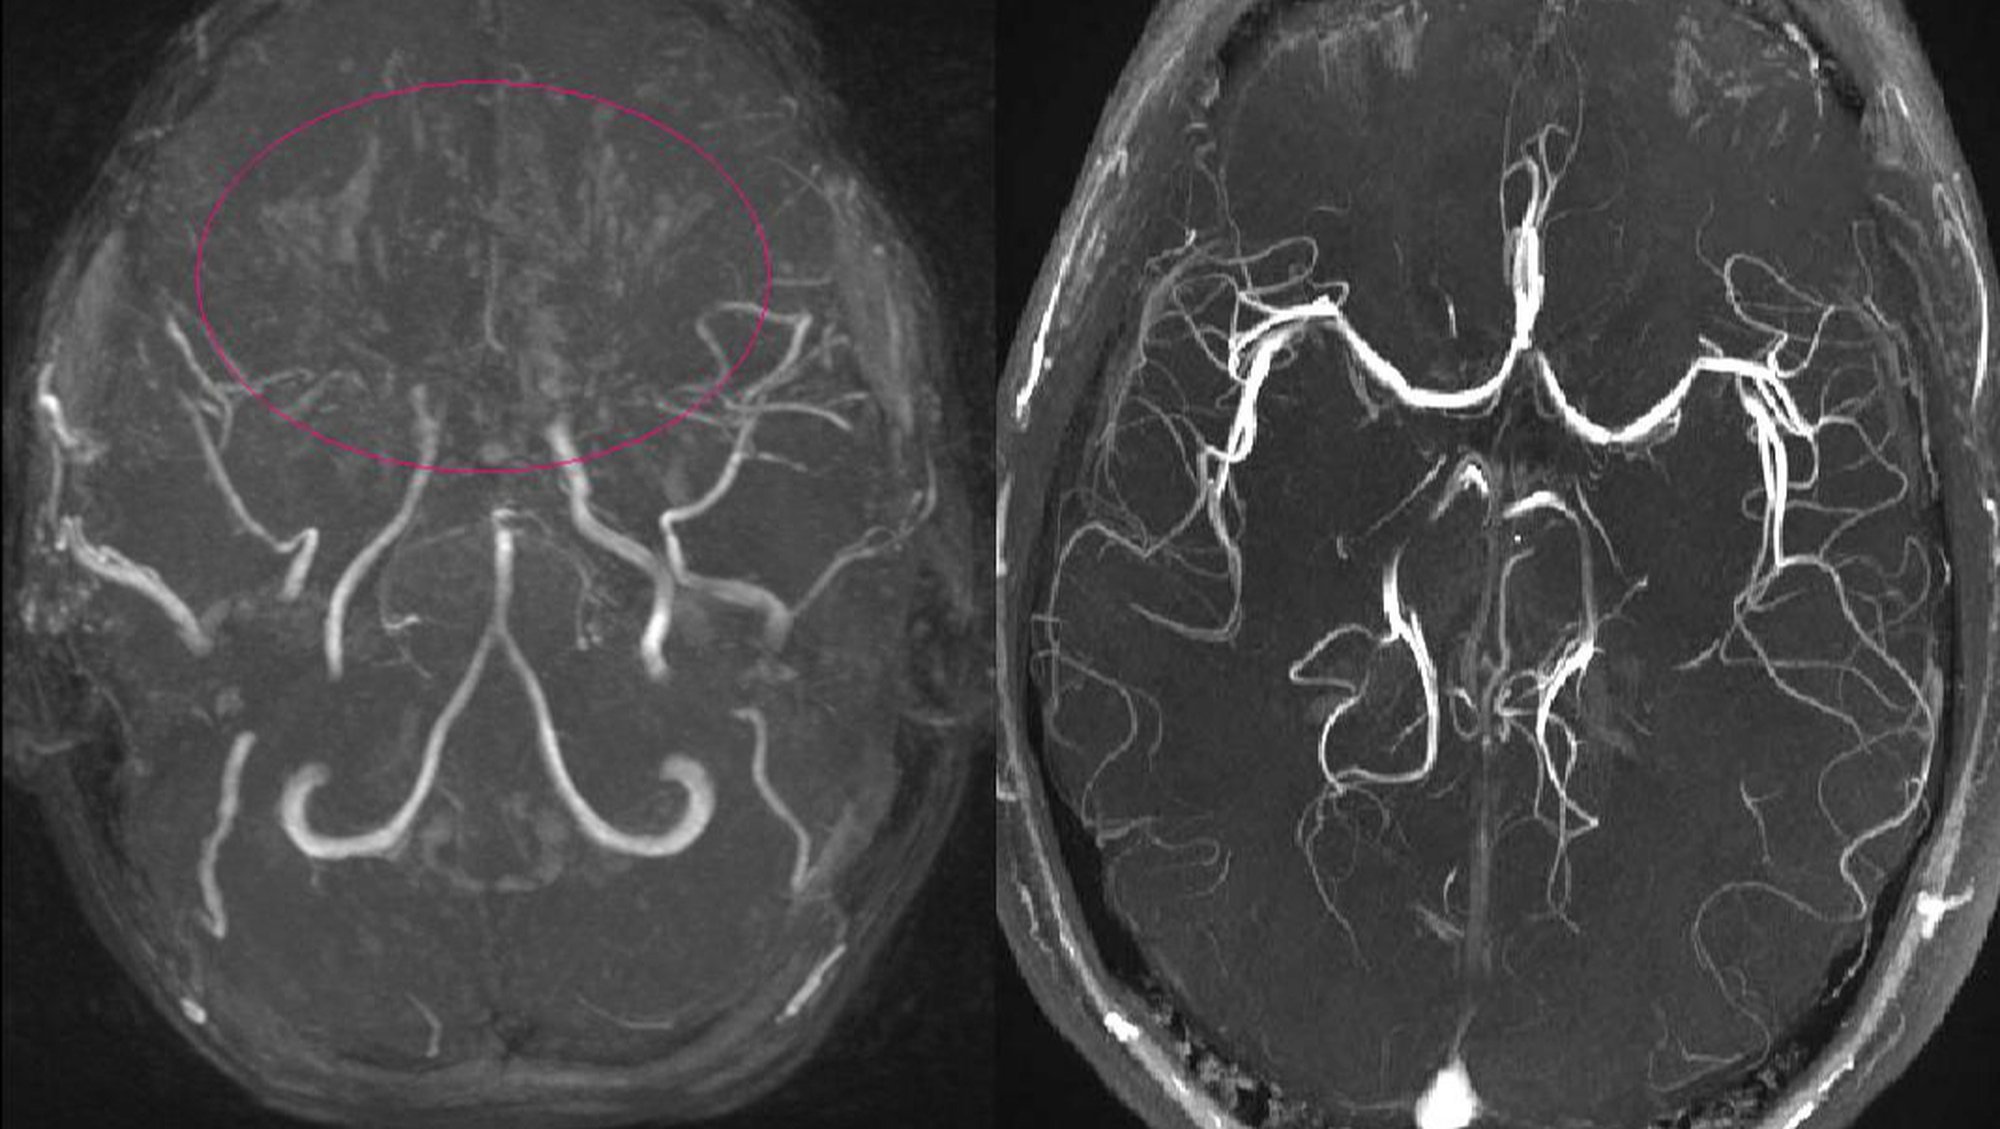

Manyetik Rezonans Anjiyografi (MRA), serebral anjiyografinin alternatifi olarak kullanılabilir. Bu yöntem, manyetik rezonans görüntüleme (MRG) prensiplerini kullanarak damarların görüntülerini oluşturur. Genellikle serebral anjiyografiye göre daha düşük risk içerir.[7]

Tanıda etkili olan bir diğer unsur, hastanın klinik belirtileri ve görüntüleme bulgularıdır. Moyamoya hastalığının belirgin bulguları genellikle supraclinoid iç karotis arterleri ve bunların proksimal dallarını içerir.[7]

Moyamoya hastalığının teşhisinde serebral anjiyografi genellikle en güvenilir yöntem olmakla birlikte, MRA gibi non-invaziv yöntemler de kullanılabilir. Teşhis sürecinde hastanın genel sağlık durumu, alerji öyküsü ve kontrast madde kullanımına karşı hassasiyet dikkate alınmalıdır. Teşhis, uzman bir sağlık profesyoneli tarafından detaylı bir değerlendirme sonucunda konmalıdır.[7]

Etimoloji

Japonca'da "havada dağılan sigara dumanı" anlamına gelen ve "moyamoya" şeklinde telaffuz edilen "もやもや" terimi, hastalığın anjiyografik görünümünden esinlenmiştir.[1], [2], [5], [8]